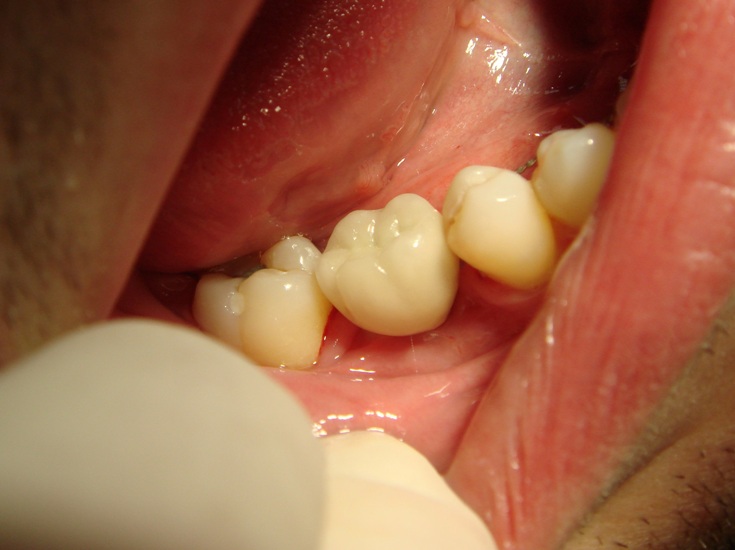

Photo 5. Oral cavity of the same patient in six months after surgery on placement of Alpha Dent Implant and restoration of dentition. There is a metal -ceramic crown placed at site of 46th tooth fixed on individual abutment.